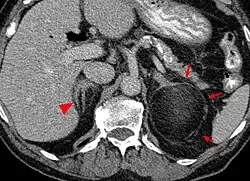

Myelolipom der linken Nebenniere (Pfeile) in der Computertomographie. Die Pfeilspitze zeigt auf die normale rechte Nebenniere.

Die Mehrzahl der Myelolipome sind asymptomatisch und werden zufällig, etwa im Rahmen radiologischer Untersuchungen oder einer Obduktion gefunden. Nur gelegentlich, insbesondere bei größeren Tumoren, berichten betroffene Patienten von Bauch- oder Flankenschmerz. Selten bestehen endokrine Störungen wie das Cushing-, Conn-Syndrom oder eine angeborene Nebennierenhyperplasie.[1]